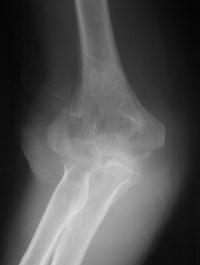

81 year old physically active woman sustained a left elbow fracture in a syncope related fall.

Lateral and central fracture component displacement.

This is seen on the lateral view to be the anterior half of the central articular surface.